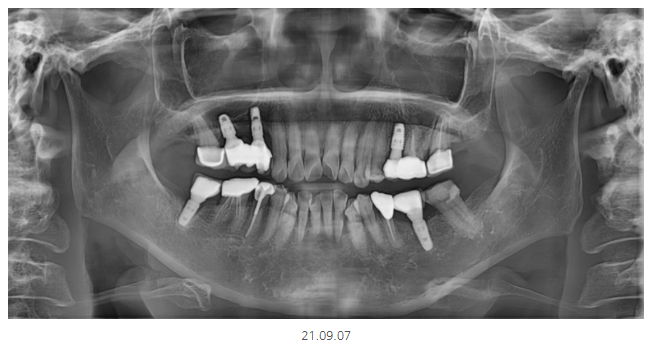

이것은 파노라마라고 하는

잇몸과 치아 전반적으로 볼 수 있는 사진인데요.

약 8,000원 정도 나오니까

최소 파노라마는 찍고 진료 보시는 것을

추천드립니다.

찍고 안찍고 검사하는데 큰 차이가 있거든요~

파노라마에서 1차 판별해 보니

의심되는 부분이 있다!!

그러면 추가 검사가 들어가게 됩니다.